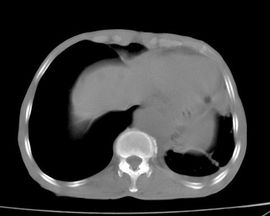

![氣喘[中醫基礎術語] 氣喘[中醫基礎術語]](/img/e/d2f/nBnauM3XzQjNwYDN5MTOyMzN0QTMwITOzEDMwADMwAjMwIzLzkzL1QzLt92YucmbvRWdo5Cd0FmLyE2LvoDc0RHa.jpg)